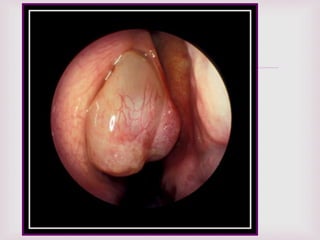

EXPLORACIÓN FÍSICA.

 Tumores con aspectos de uva.

 Se pueden encontrar en ambas fosas

nasales.

 Pueden adoptar la forma de la región

anatómica donde se encuentran.

 Blandos, tersos, translucidos.

 Ulceraciones con sangrado en ocasiones.

 Se encuentran en la parte superior de la

cavidad nasal y proceden del complejo

osteomeatal.

 La rinoscopia anterior

confirmara la presencia

de pólipos.

 Características macroscópicas de

los pólipos nasales…



POLIPO NASAL